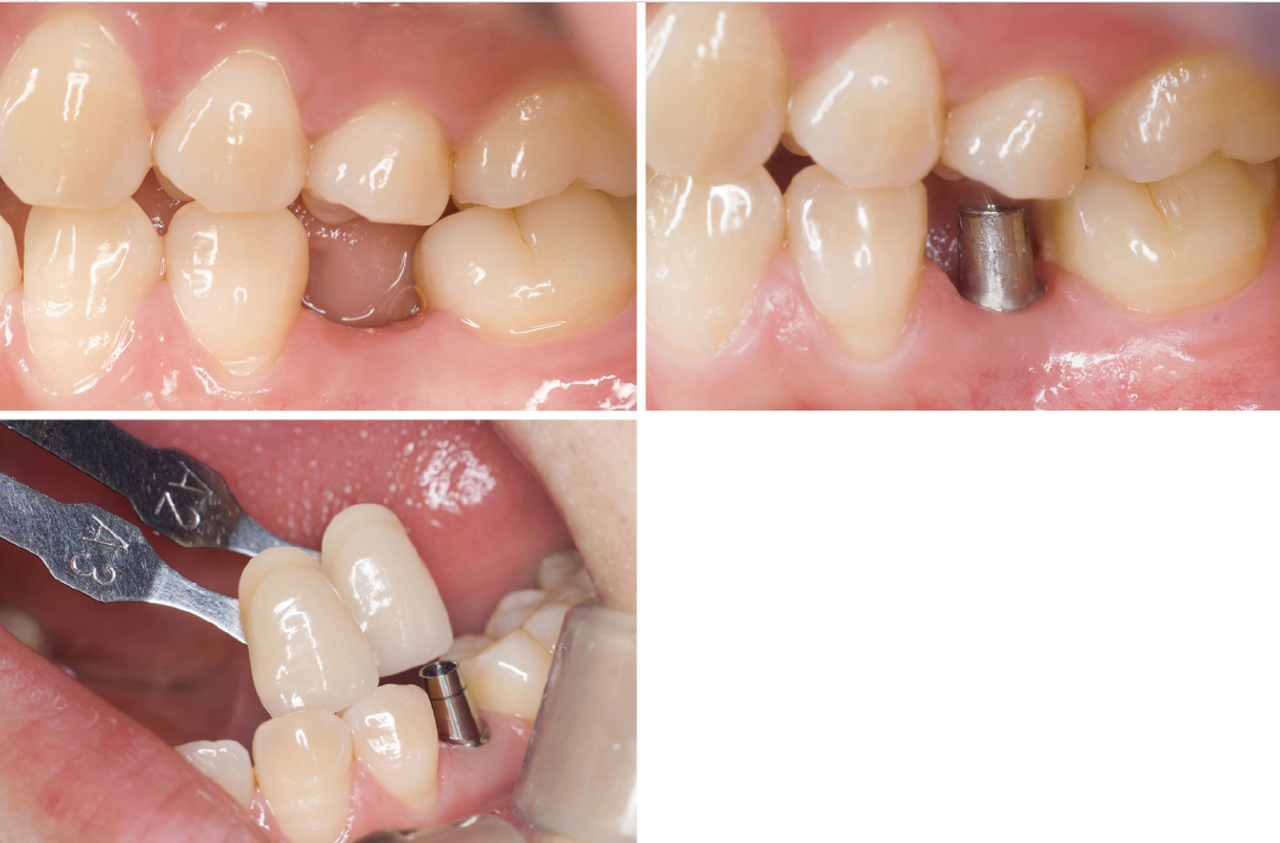

#12 zirconia 보철

인접치와 유사한 보철을 제작하려면 어떻게 기공의뢰서를 작성해야 할까?

이 증례처럼 D계열 색상에 노란색 수평 줄무늬가 있는 치아는 보철물 제작이 어렵다. 정확한 기저색 선택 후 shade tab과 치아를 촬영한 임 상 사진을 치과기공사에게 전달해야 한다.